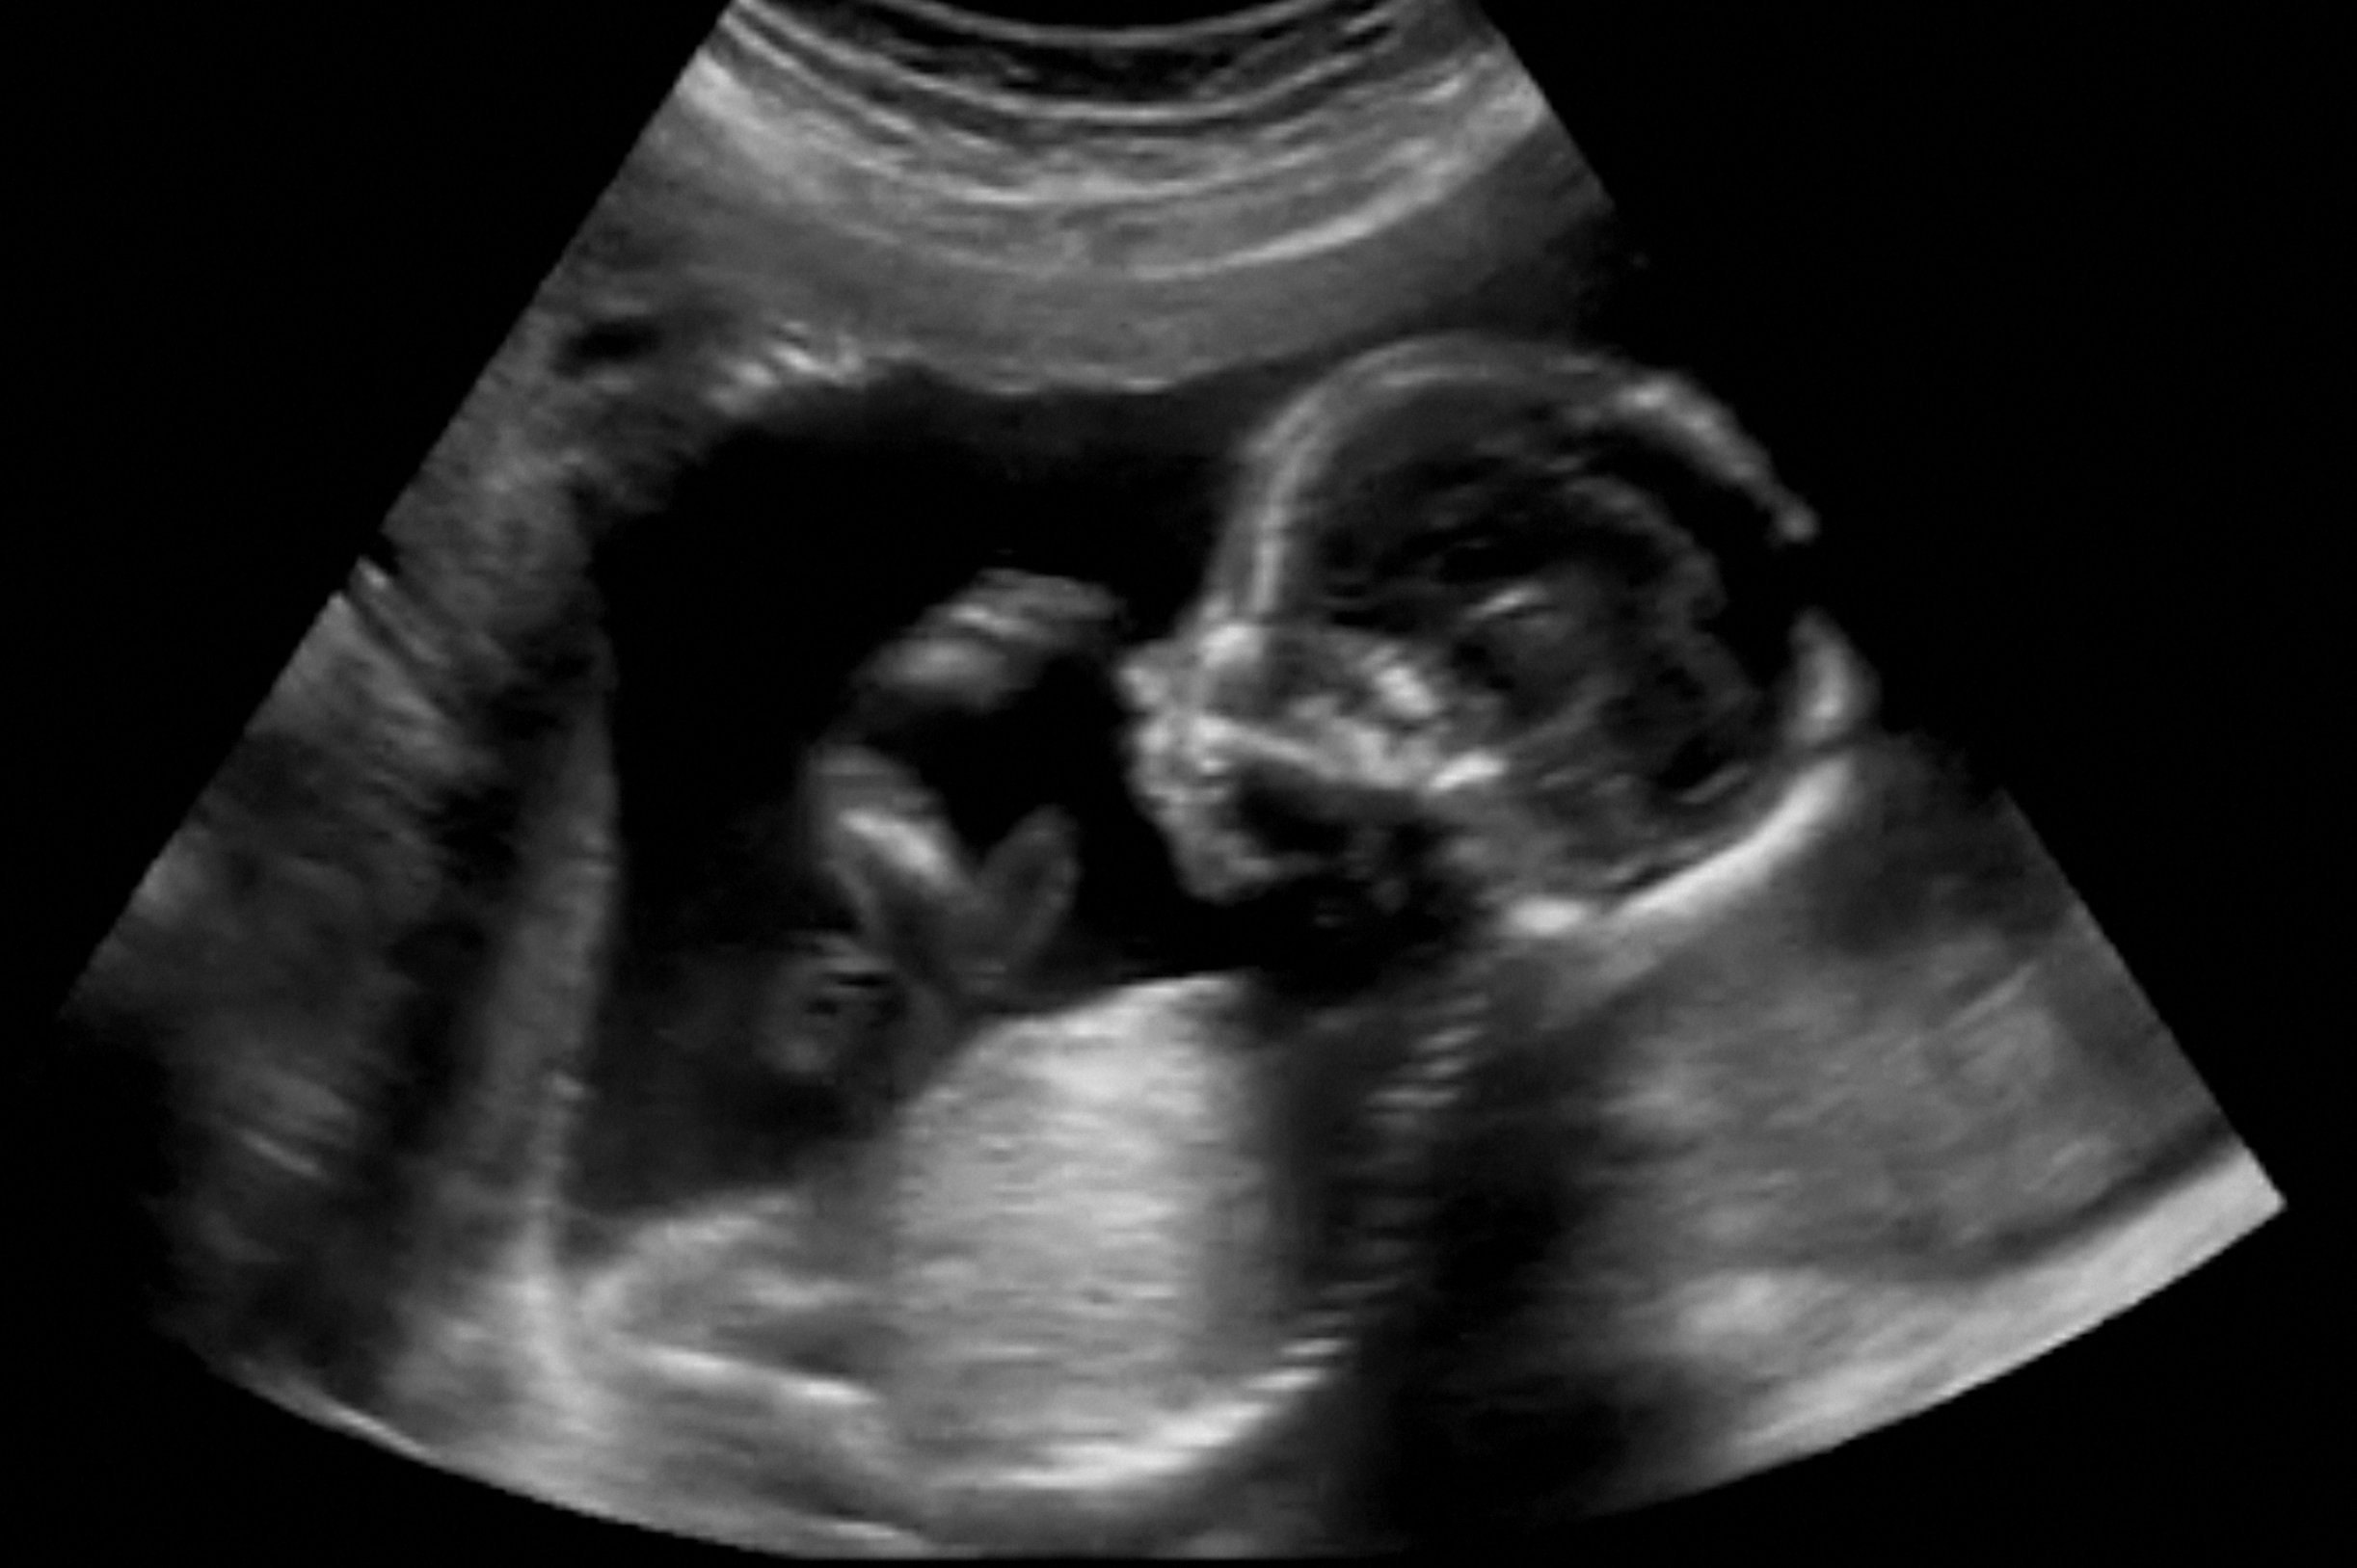

(Vienna, 4th December 2019) If pregnant women take significant amounts of the psychostimulants coffee, nicotine and amphetamine during pregnancy, their children have a higher risk of developing neurological and psychiatric problems later in life. Researchers at MedUni Vienna’s Center for Brain Research have now successfully identified the regions of the brain that act as "hot spots" for psychostimulants and discovered that the mother's reactions to these substances are substantially different from those of their baby. This study has now been published in the multidisciplinary journal PNAS.

Drug abuse during pregnancy carries a considerable risk and negatively impacts foetal development. Even though the mother does not react particularly strongly to certain psychostimulants, these drugs can nonetheless permanently affect brain development of her baby or child.

The precise areas of the brain that are affected by maternal drug consumption were hitherto unknown. The recent study conducted by MedUni Vienna’s Center for Brain Research, working in conjunction with the swedish Karolinska Institute, has now shown that episodic exposure to amphetamine, nicotine or caffeine during pregnancy triggers an extensive malfunction in the foetal brain, which specifically affects the development of the indusium griseum (IG). The IG is a cerebral area that reacted to all psychostimulants tested in a mouse model.